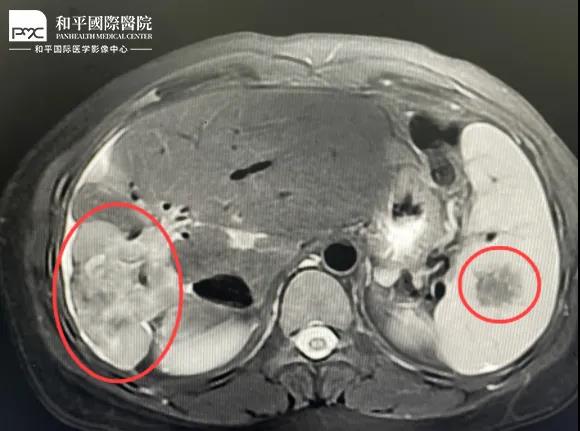

檢查結(jié)果對于這家人而言猶如晴天霹靂,經(jīng)核磁共振等相關(guān)檢查,當(dāng)?shù)蒯t(yī)生懷疑是肝癌,建議手術(shù)治療。悲痛中,家人們對這樣的結(jié)果表示無法接受,想要多去幾家醫(yī)院看看,為了進(jìn)一步確診,王小姐來到我院醫(yī)學(xué)影像中心進(jìn)行檢查,事情竟發(fā)生了戲劇性反轉(zhuǎn)

根據(jù)影片分析,結(jié)合王小姐有系統(tǒng)性紅斑狼瘡的病史,長期服用激素,免疫力低下,近期又有低熱盜汗的癥狀,影像中心執(zhí)行主任侯文杰初步判斷王小姐是得了肝結(jié)核,并不是肝癌!

由于肝結(jié)核是臨床非常少見的病例,單靠影像診斷是很難診斷正確的,在侯主任的建議下,王小姐做了穿刺活檢,診斷結(jié)果的確是肝結(jié)核